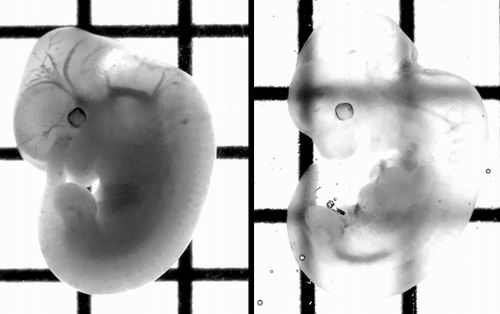

图右处理后的组织样本明显更加清晰。图片来源:《自然—神经科学》

在糖水调和液中经历了3天的浸泡使原本不透明的组织(图左)变得清晰起来(图右),这项工作为科学家探究大脑和其他器官的内部运行提供了可能。